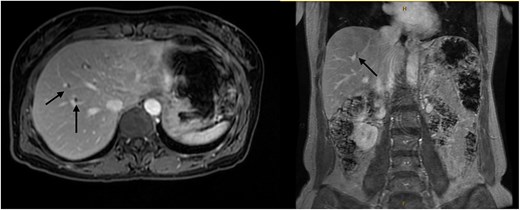

A 54-year-old female with a recent diagnosis of IBD complicated by PSC, presenting with right upper quadrant pain, underwent abdominal ultrasound, and magnetic resonance cholangiopancreatography (MRCP) as part of her PSC workup. Ultrasound demonstrated two 7 mm gallbladder polyps, with a normal gallbladder wall. MRCP demonstrated segmental intrahepatic duct dilatation in segments II and VIII in keeping with PSC (Fig. 1). Initial liver function tests and Ca 19.9 level showed only a mildly elevated GGT and ALP. Due to the recent diagnosis of IBD and small size of gallbladder polyps, observation with progress imaging at 12 months was undertaken. Repeat MRCP demonstrated a slight outpouching of the wall of the gallbladder with subtle enhancement of the lateral wall, with no concerning features for malignancy.

Magnetic resonance imaging liver/MRCP demonstrating subtle intrahepatic biliary dilatation (arrows), most pronounced in segment 8.